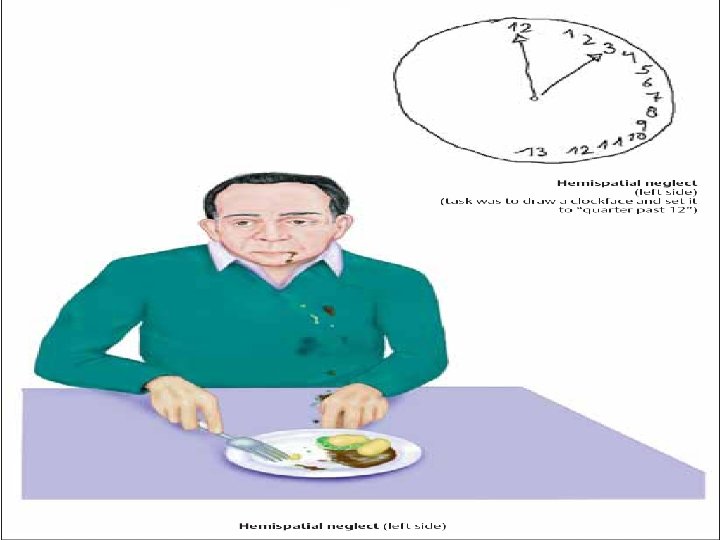

В бассейне А. cerebri posterior Зрительная агнозия Алексия Таламический синдром Альтернирую- щий синдром Вебера

В бассейне А. cerebri posterior Зрительная агнозия Алексия Таламический синдром Альтернирую- щий синдром Вебера